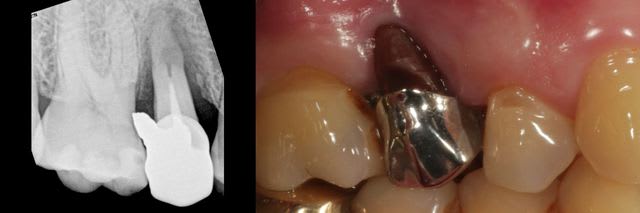

Cette patiente vient me voir pour trouver une solution pour sa 15, que proposez vous?

la dent a eu une résection apicale à l'ancienne il y a quelques années, est mobile, plus d'os en vestibulaire : No way!